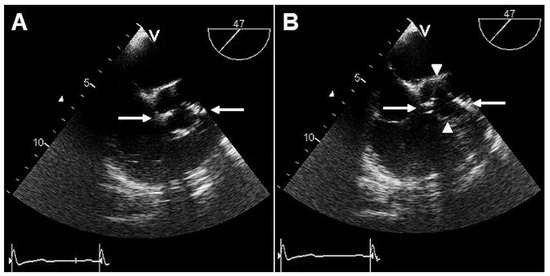

Double Raphed Bicuspid Aortic Valve and the “Reverse S” Coronary Angiographic Sign

Case report